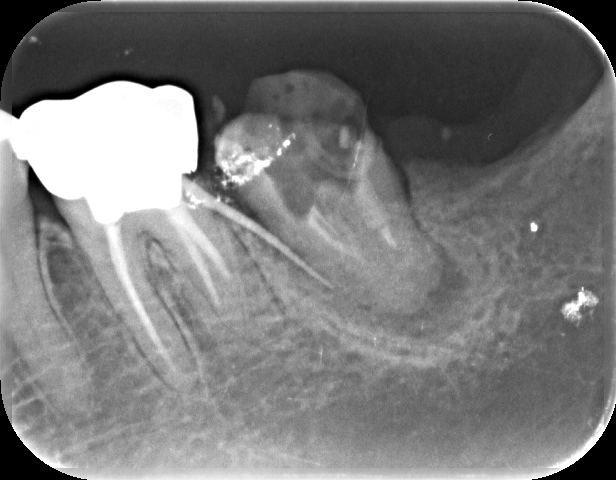

左下他院で抜歯と言われて、セカンドオピニオンで来院されました

before

| ① 患者様の主訴 | 左下腫れている |

| ② 診断結果 | 慢性化膿性根尖性歯周炎 |

| ③ 治療内容 | マイクロスコープ、ラバーダムを使用した精密根管治療 |

| ④ 治療後経過 | 術後5年、経過良好 |

| ⑤ 治療期間 | 1ヶ月 |

| ⑥ 治療費用 | 165,000円 |

| ⑦ リスク・副作用 | 歯根破折や病変再燃の場合は抜歯または外科的歯内療法 |